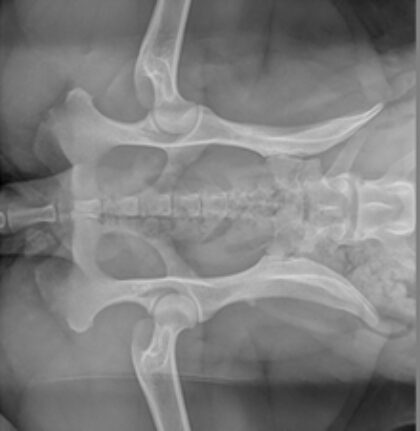

Der Übergangswirbel beim Hund

Eine häufige Diagnose nach der HD Beurteilung ist ein Übergangswirbel. Jeder redet davon aber was ist das eingentlich? Warum ist ein zusätzlicher Lenden- oder Sakralwirbel problematisch? Man redet von einer vererbbaren Veränderung. Aber was bedeutet das für diesen Hund und kann eine Erkrankung vermieden werden? Was bringt mir eigentlich ein Röntgenbild? Und braucht es ein MRI oder eine Überweisung zum Neurologen?